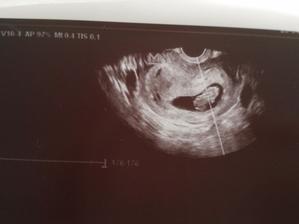

26.4 kontrola miminko odpovídá 9+2 jsme objednáni na screening na 17.5.2017